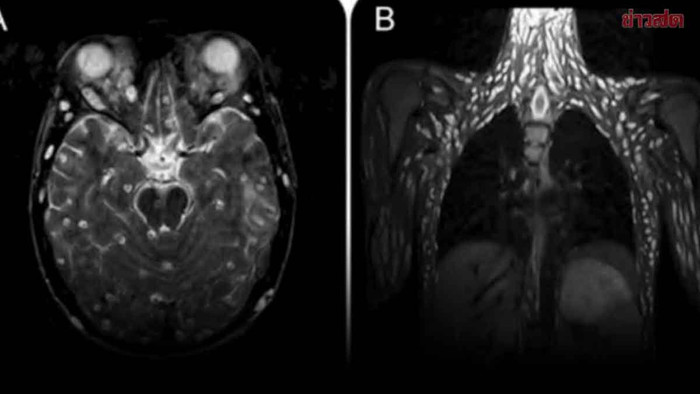

Theo nội dung được chia sẻ, một bệnh nhân đã nhập viện trong tình trạng đau đầu dữ dội, nôn mửa và co giật liên tục. Kết quả chụp MRI khiến các bác sĩ choáng váng: nang sán dây lợn đã lan rộng khắp cơ thể bệnh nhân, bao gồm cả não và các nhóm cơ. Đây là một dạng nhiễm ký sinh trùng hiếm gặp nhưng cực kỳ nguy hiểm, thường được gọi là “bệnh ấu trùng sán dây lợn lan tỏa”.

Ăn rau sống, cô gái bị sán dây lợn 'xâm chiếm' cơ thể Ảnh 1